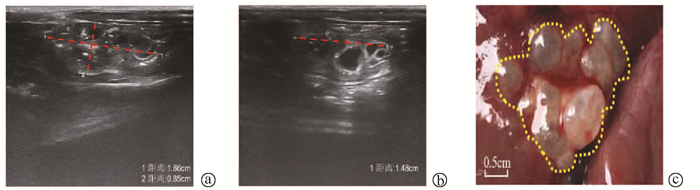

Expert consensus on the imaging diagnosis of hepatic echinococcosis

Radiology of Infection Sub-branch, Radiology Branch, Chinese Medical Association, Committee on Radiology of Infectious, Radiology Branch, Chinese Medical Doctor Association

2021, 37(4): 792-797. DOI: 10.3969/j.issn.1001-5256.2021.04.014

Abstract(1244) HTML (604) PDF (2065KB)(121)

Abstract:

Echinococcosis is a zoonotic disease with global distribution and has become an issue seriously affecting public health around the world. Imaging technology plays an important role in the early diagnosis, preoperative evaluation, and treatment outcome monitoring of hepatic echinococcosis. At present, no consensus has been reached on the imaging diagnosis of echinococcosis, which brings difficulties in the learning and training of imaging professionals and the standard diagnosis and treatment of echinococcosis in clinical practice. For this reason, Beijing YouAn Hospital, Capital Medical University, and The First Affiliated Hospital of Xinjiang Medical University organized the radiologists engaged in infection and inflammation from several hospitals to reach a consensus on the basis, principles, and criteria for the imaging diagnosis of echinococcosis and the differential diagnosis of echinococcosis, with reference to international guidelines, related articles, the latest research findings in China and globally, and the methodological requirements for the establishment of guidelines and standards in evidence-based medicine, so as to provide a clear diagnostic basis for clinicians in the clinical application of hepatic echinococcosis imaging.